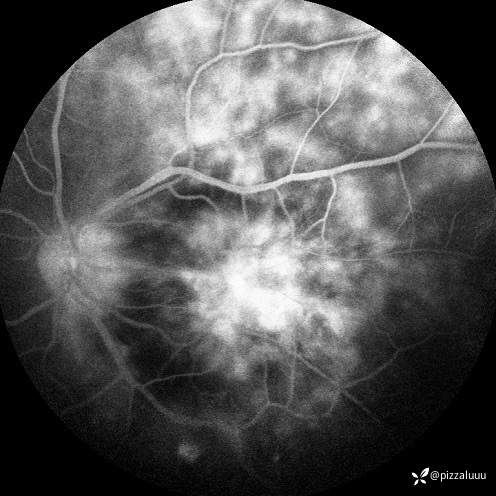

今天补充了FFA、AF和眼底照相。很典型的coats,后极部视网膜可见块状不规则而隆起的黄色渗出。AF可见病灶处低自发荧光。FFA所见:视网膜毛细血管扩张迂曲及异常血管形态,以小动脉明显,管壁呈囊样扩张,有梭形、串珠样动脉瘤。大片无灌注区。异常血管早期渗漏明显,形成强荧光斑,晚期荧光融合。由于大片黄白色渗出位于外丛状层,对视网膜血管荧光影响不大。可看到脉络膜背景荧光遮蔽。